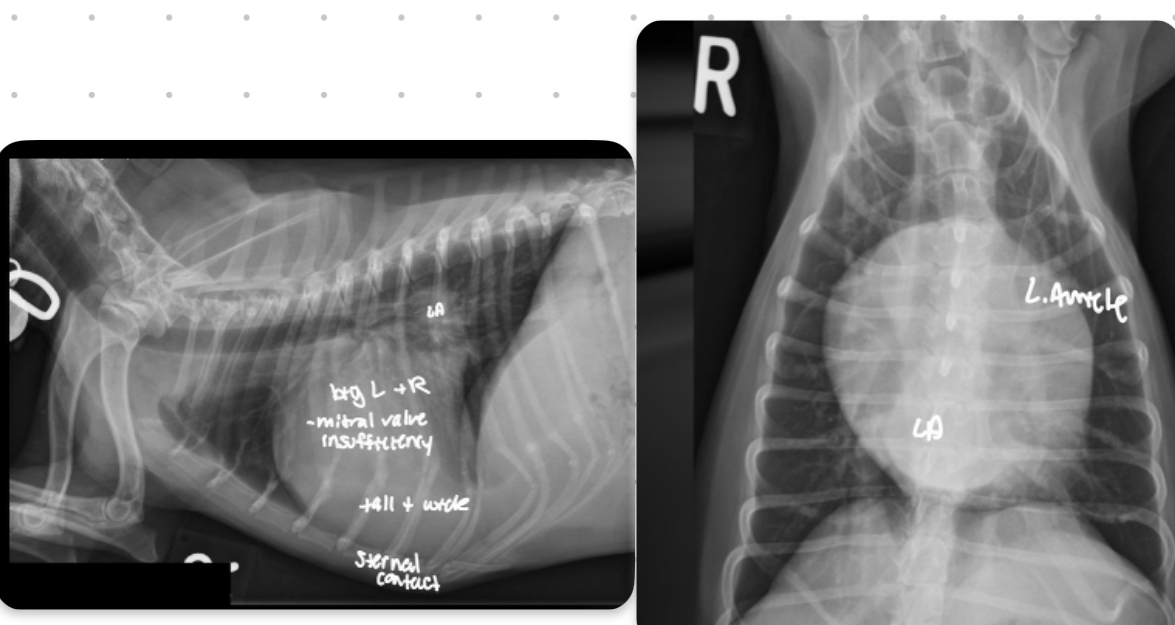

Features of generalized cardiomegaly in dogs and what disease is associated with this?

-combo roentgen signs involving L and R cardiac chambers

-dogs often get mitral dz which results in both L+R heart enlargement

-tall + wide, sternal contact

what part of the heart is enlarged in this dog

Generalized (whole thing)